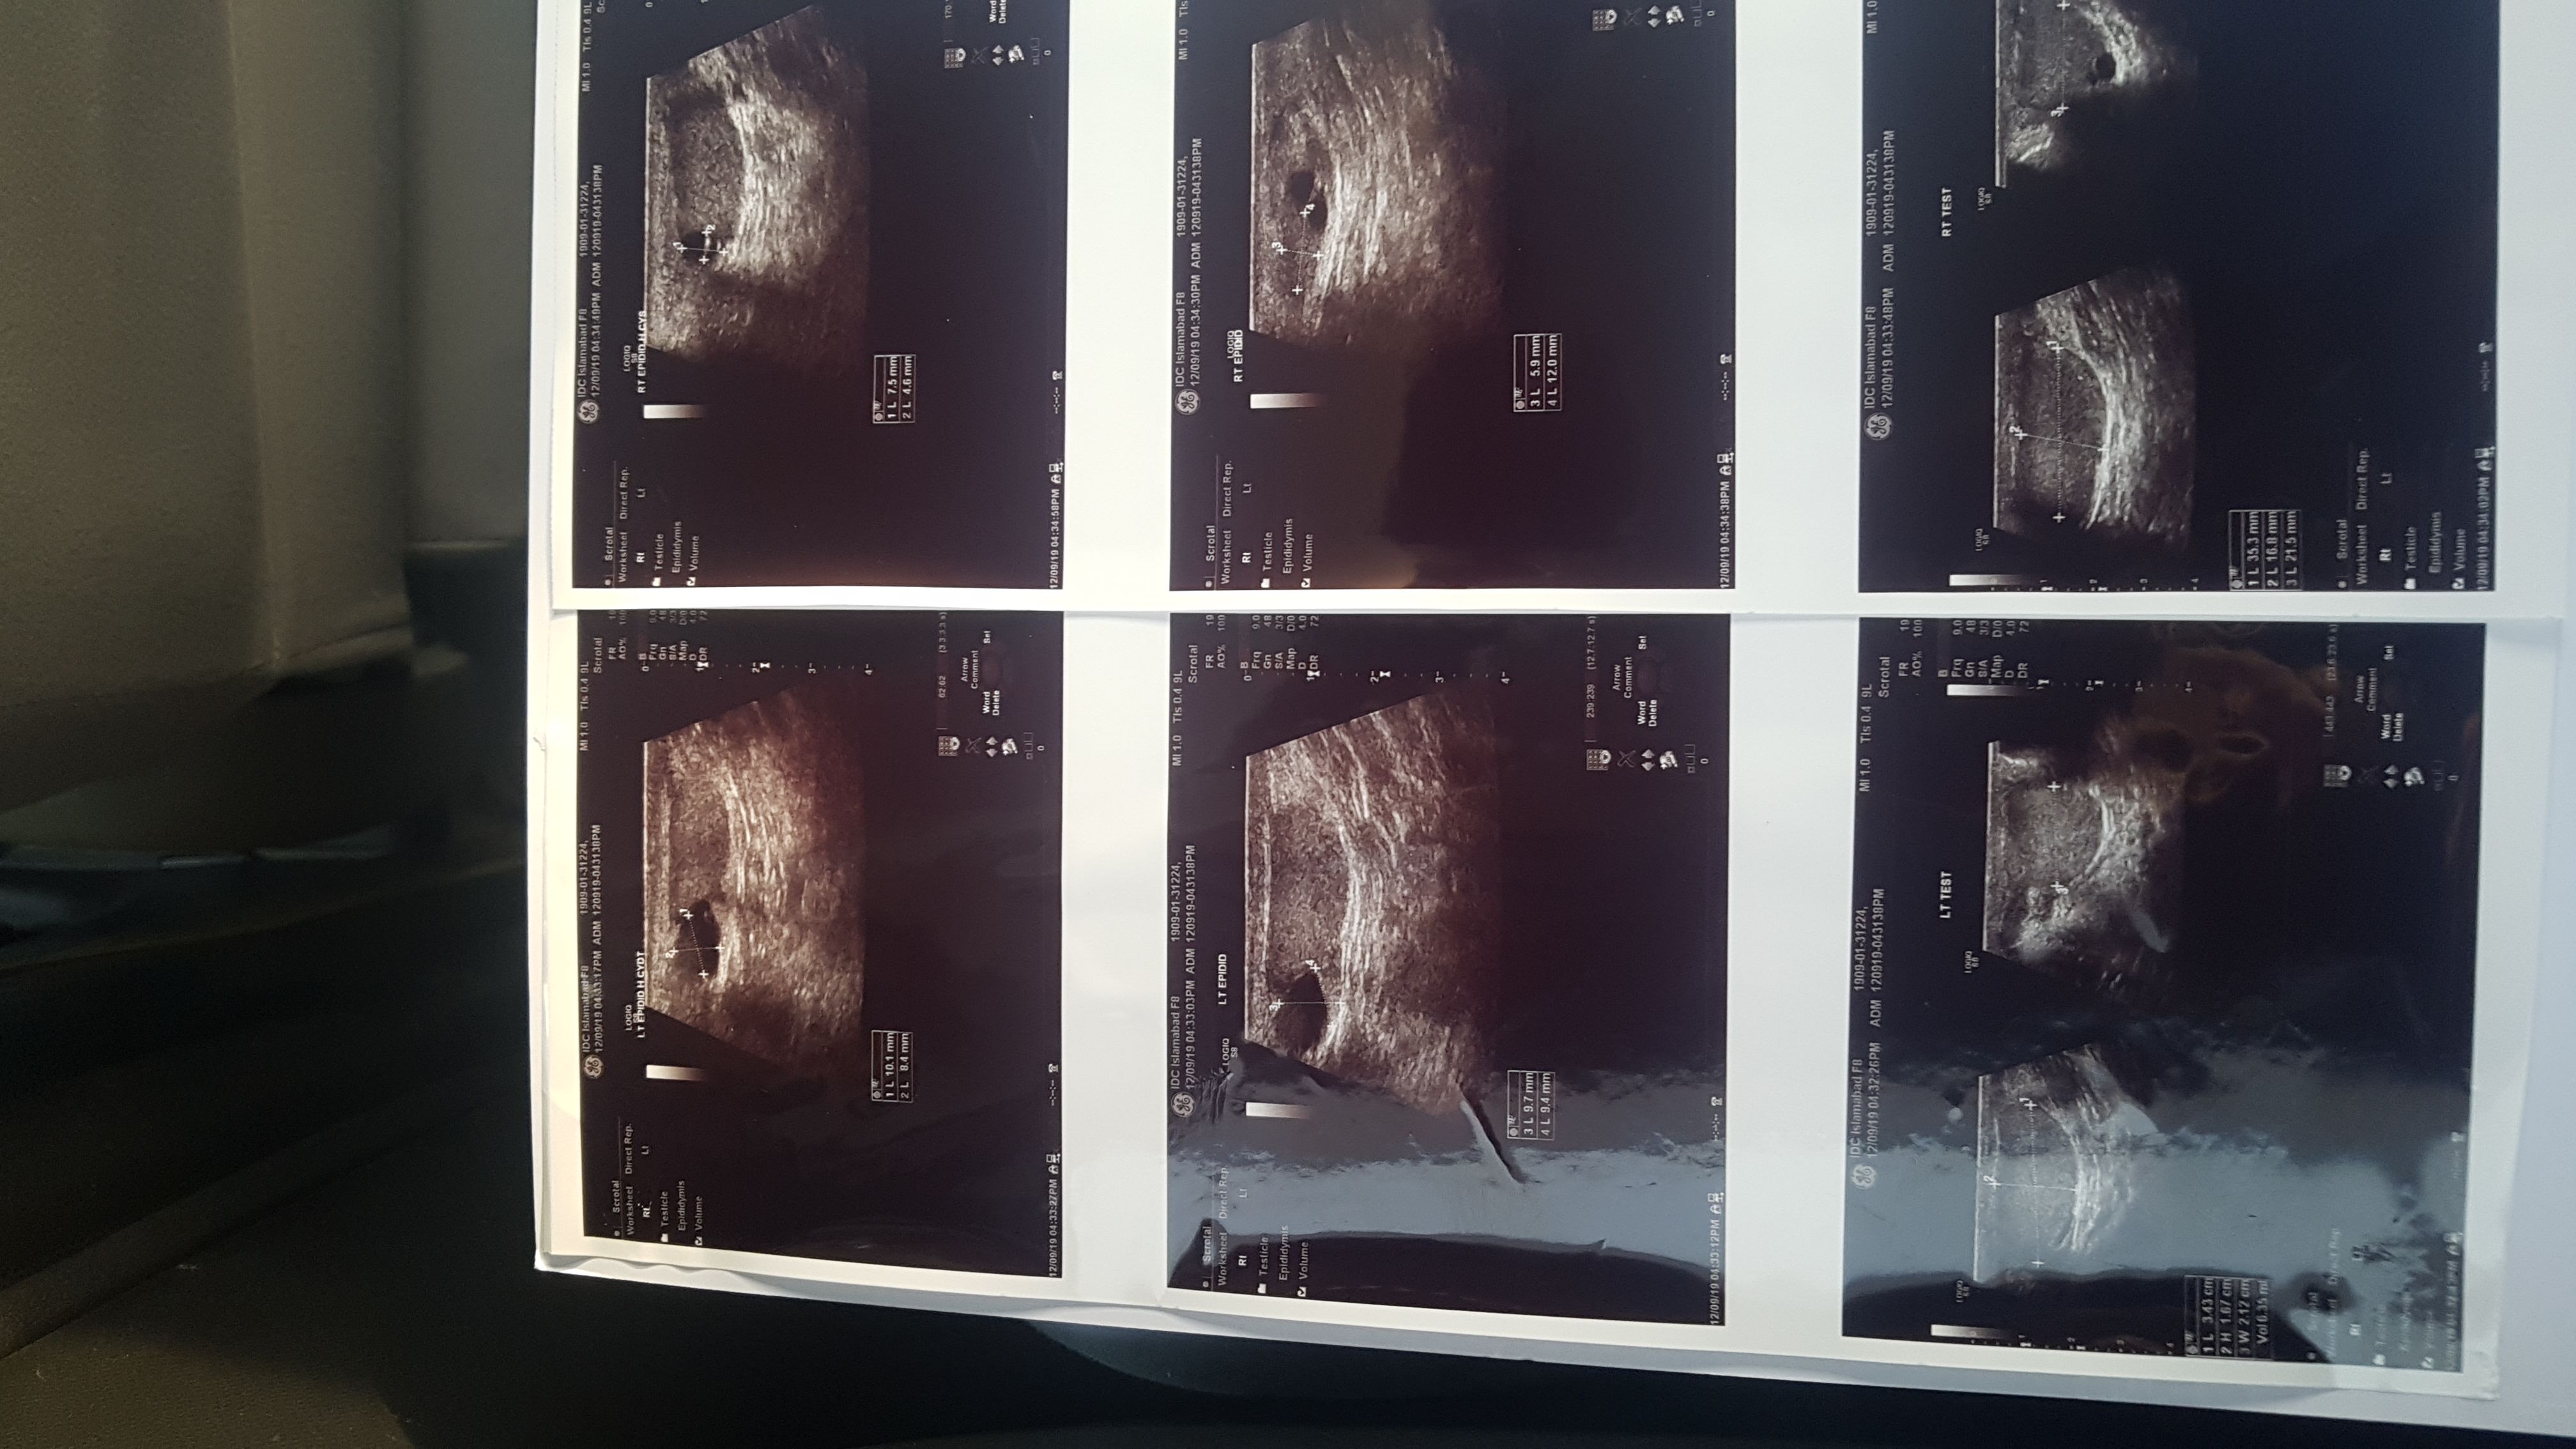

AOA. Muhammad Bilal here, and married for the last 9 months, recently had semen analysis and got nil sperm count, also i have been operated twice in childhood for undescended testis. Also had blood test carried out for FSH and LH Levels FSH is 23.3 LH is 6.8 Yesterday i went for Doppler ultrasound and found out i had cyst on both head of epidymisis. I am worried and cant figure out what to do for the past 3 weeks. Had checkup in CMH Rawalpindi. Can i have ur personal number to discuss more and also i will visit your place for proper chkup and treatment

Your hormones and ultrasound are normal. Obstructive azospermia.

You need assisted reproductive technique to get sperm

latest report of testosterone and fsh level

fsh report